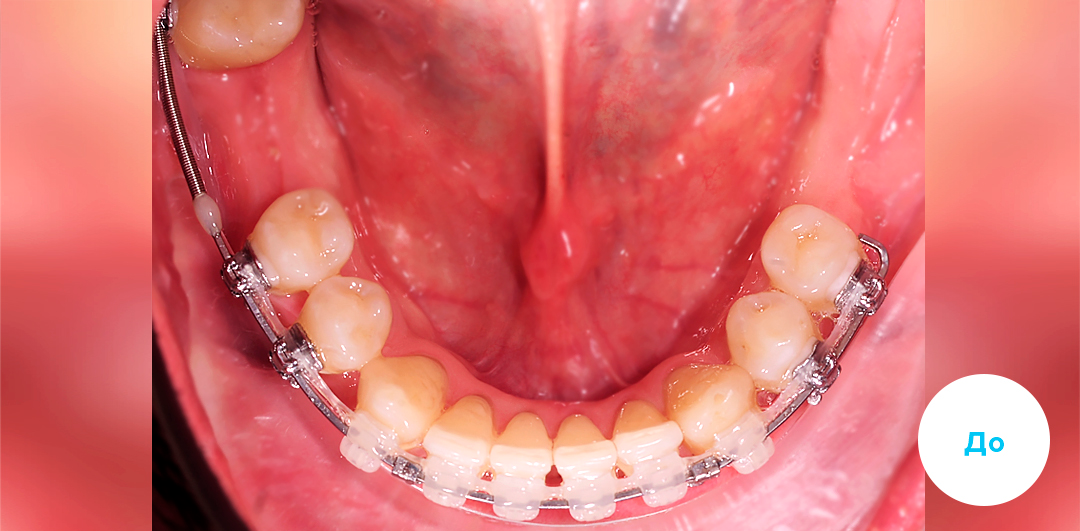

Ортодонтический аппарат Марко-Росса

Ортодонтический аппарат Марко-Росса

В приведенном клиническом случае ортодонты использовали индивидуальную цифровую брекет-систему INSIGNIA на базе керамических брекетов Damon Clear

Клинический случай

Подробнее о лечении:

Пациенту 39 лет. Выполнено удаление по терапевтическим показаниям зубов 4.6, 3.7 и 3.8 Имплантация проведена через 1.5 года после начала ортодонтического лечения. Параллельно проводилось закрытие промежутков на верхней челюсти задними зубами путем перемещения к мини-имплантатам Ортодонтическое лечение проводилось индивидуальной цифровой брекет-системой INSIGNIA (Инсигния), на базе керамических брекетов Damon Clear на обеих челюстях.